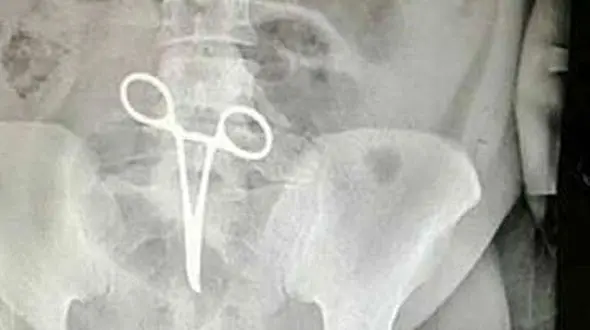

حوادث رکنا: رئیس بیمارستان شهید بهشتی اردستان گفت: اشتباهی که در بیمارستان اردستان اتفاق افتاده است یکی از موارد نادر پزشکی است که متأسفانه رسانهای شد.

حوادث رکنا: مدیر روابط عمومی دانشگاه علوم پزشکی اصفهان در خصوص اشتباه پزشکی در یکی از بیمارستانهای اردستان توضیح داد.